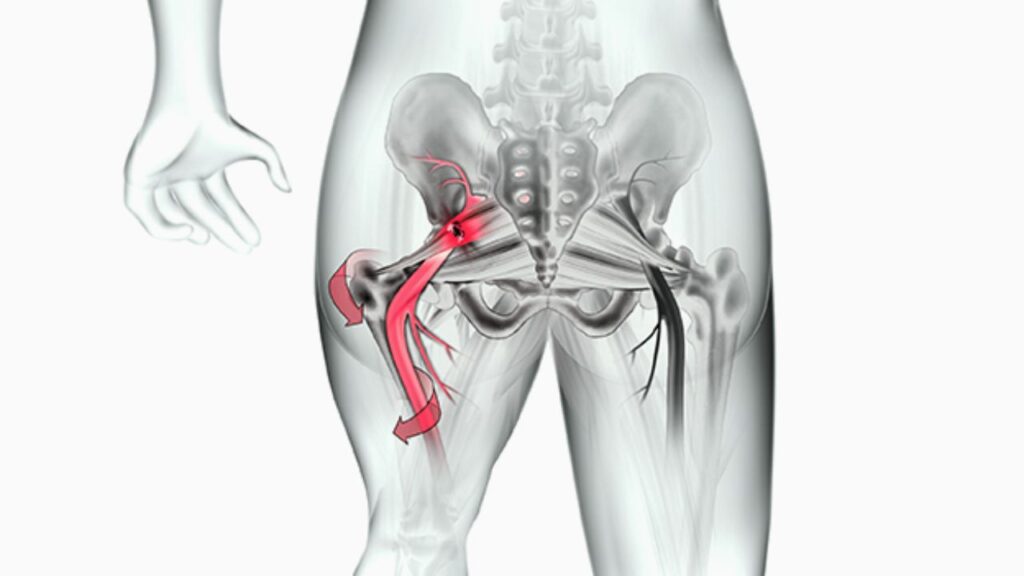

A cirurgia é uma opção rara, indicada apenas para os casos mais graves e refratários, que não respondem a nenhum outro tipo de tratamento. O procedimento consiste na liberação cirúrgica do músculo piriforme para descomprimir o nervo ciático, aliviando a pressão de forma definitiva.